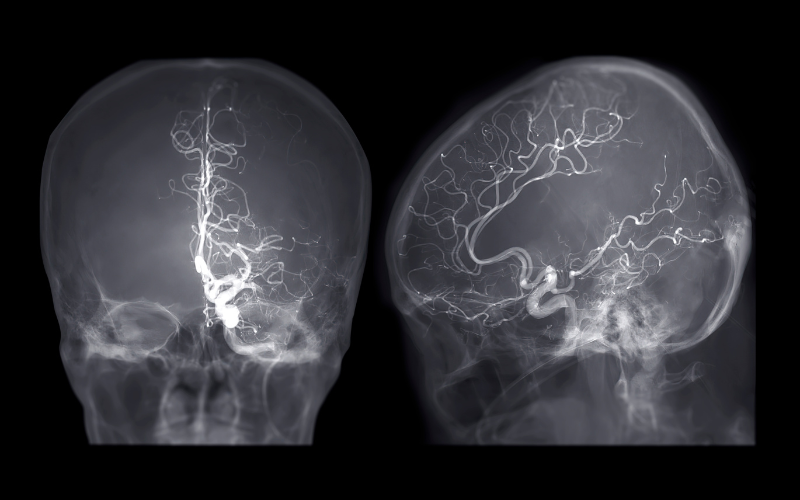

Epilepsy surgery begins with a comprehensive pre-surgical evaluation, including long-term video EEG monitoring, high-resolution MRI, PET scans, and neuropsychological assessments. This helps localize the exact region of the brain responsible for seizures.